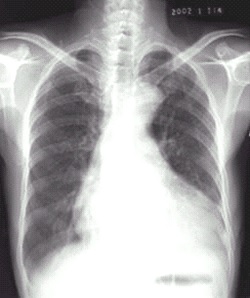

03卷-4.病史:女性,73歲,血壓升高10年,心悸、頭暈、乏力2周。診斷(本題滿分2.00分)

A.梨形心

B.靴形心

C.普大型心臟

D.正常心臟

本題答案:B

題目解析:【該題針對(duì)“X線-心臟增大(二尖瓣型、主動(dòng)脈型和普大型)”知識(shí)點(diǎn)進(jìn)行考核】